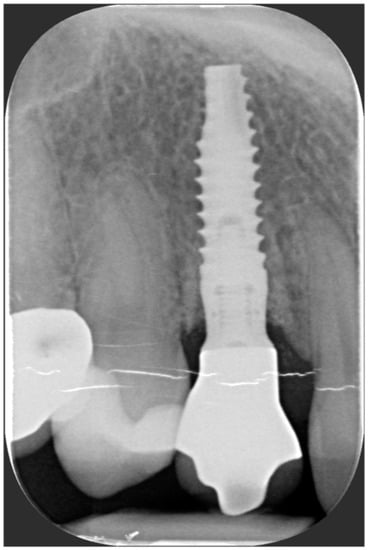

A 40-year-old patient presented with an endodontic fistula on the maxillary right canine (Figure 1a–c). Radiographic evaluation revealed internal root resorption (Figure 2). The medical history did not include any systemic conditions contraindicating implant placement or regenerative surgery. The patient did not suffer from any form of periodontal disease. Due to the extension of root resorption, the tooth was considered irrational to treat, and the treatment plan consisted of extraction and immediate implant positioning.

Figure 2. Radiographic evaluation revealing internal root resorption.